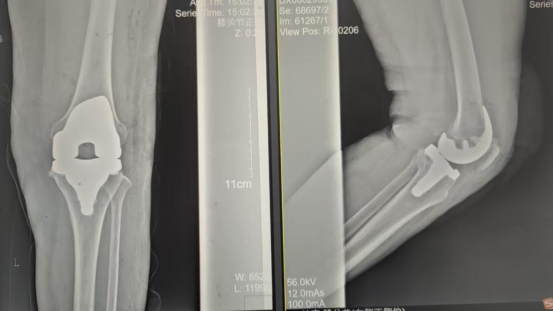

術(shù)后影像資料

手術(shù)當(dāng)天張女士懷著忐忑的心情進(jìn)入手術(shù)室,然而伴隨著麻醉醫(yī)師的和藹交談和手術(shù)護(hù)士的溫馨叮嚀,在不知不覺中慢慢睡著,手術(shù)非常順利。術(shù)后經(jīng)醫(yī)護(hù)人員的精心治療與護(hù)理,張女士康復(fù)出院,最終解決了10余年的病痛。

因張女士患有高血壓病2級(高危)、心律失常(竇緩)且伴有肺部感染等并發(fā)癥。穆志亮主任和葉龍安主治醫(yī)師根據(jù)張女士的病情制定詳細(xì)手術(shù)方案,建議在全麻下行“左人工全膝關(guān)節(jié)置換術(shù)”。